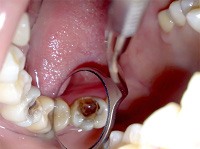

Часто некроз пульпы развивается бессимптомно. Может обнаруживаться случайно при проведении рентгенологического исследования (ортопантомограммы, компьютерной томографии). В таком случае некроз часто сочетается с изменениями в периапикальных тканях зуба. В некоторых случаях пациент обращается к стоматологу с жалобами на изменение цвета зуба. При осмотре полости рта стоматолог обнаруживает зуб серого цвета. При вскрытии пульпарной камеры определяется гнилостный запах. Перкуссия таких зубов бывает положительной. Поверхностные слои пульпы грязно-серого цвета, не кровоточат. Зондирование корневой пульпы также может быть положительно.